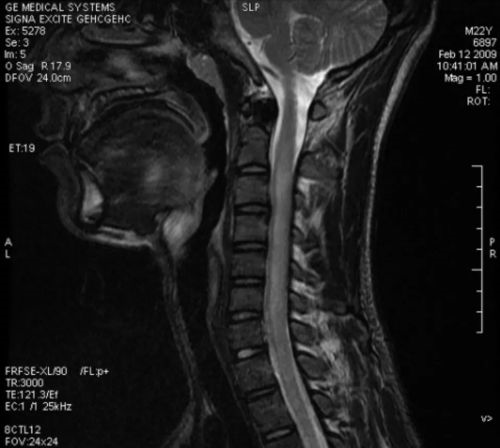

虽然强生还没有公布暂停疫苗的原因,但美国范德比尔特大学医学院传染病教授认为,有可能是比心脏病、前列腺癌、糖尿病等更严重的副作用,也有可能是神经系统受到了伤害。 事实上,一名9月份出事的牛津疫苗接种志愿者证实患上横贯性脊髓炎。

而该疫苗研发项目在英国暂停大约一周后恢复了研究,此后在其他国家也重新开始了研究。 然而,在美国,这项研究仍被搁置。 引人深思的是,出事的志愿者患上的是上文提及的横贯性脊髓炎。

这是由于原因不明的感染直接引起或感染诱发所引起的脊髓功能失常导致全部或大多数神经束的神经冲动传导阻滞,局限于数个节段的急性横贯性脊髓炎症。 多数在急性感染或疫苗接种后发病。表现为脊髓病变水平以下的肢体瘫痪,感觉缺失和膀胱、直肠、植物神经功能障碍。 阿斯利康正在测试的疫苗,称为牛津疫苗,是与英国牛津大学共同研发的。 此前,该疫苗正在英国、美国、巴西和南非进行三期试验。